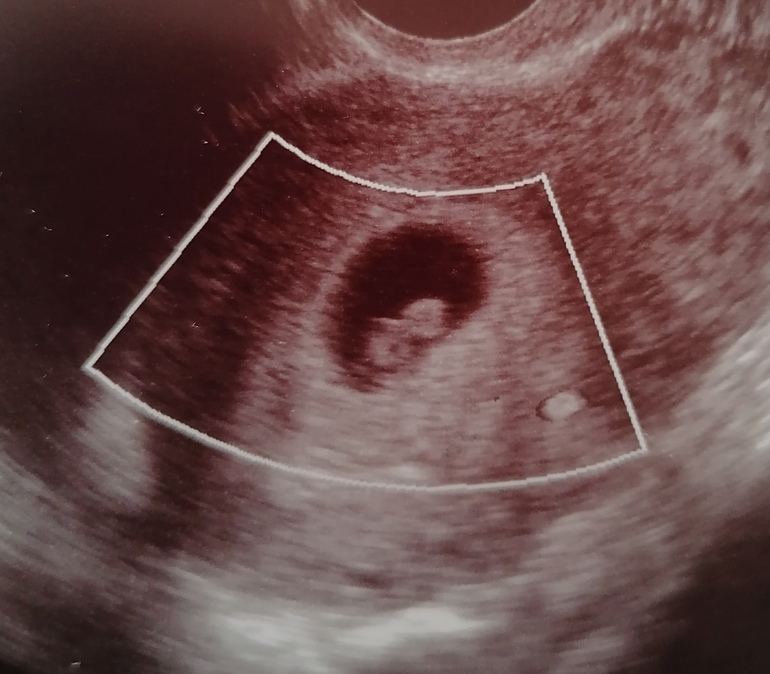

Ктр плода

Такой же ктр был в 8 акушерских,поставили по узи 8+2

У вас опережает)) срок по ктр на 8+3 примерно соответсвует.

ктр 18 скорее на 8 недель

У меня в 7.6 был ктр на 7.5 - 14мм. У вас опережает малыш значит, т.к срок по ктр больше. И да, таблицы в помощь))) может Вам в первый раз намеряли меньше или сейчас больше? Мне кажется слишком большой рост за 6 дней....хотя я не врач, не знаю))

Спасибо) Честно, даже не знаю, вот фото сегодня дали)